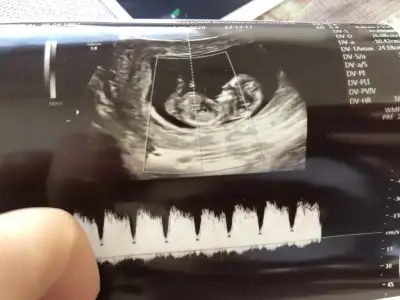

13+4 sizce kız mı erkek mi?